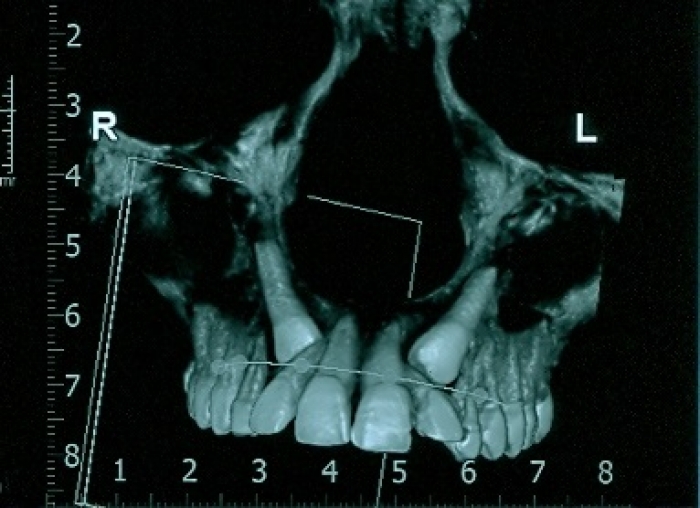

Tomografia - caninos inclusos